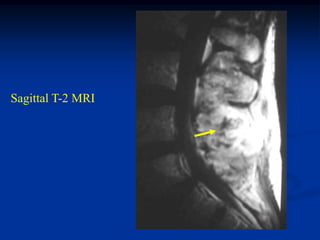

Case #218

58 year female

adamantinoma

proximal tibia

Lateral view

Bone scan

Coronal Gad

Contrast MRI

Sagittal STIR MRI

Axial T-2 MRI

Another axial T-2 MRI showing cystic fluid-fluid levels